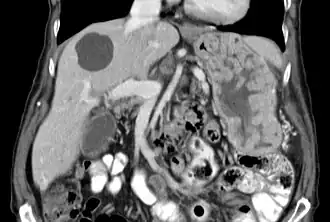

| Biopsy of the stomach in Ménétrier disease; the substantial pit hyperplasia makes the large rugal folds appear to be covered by myriad polyps resembling hyperplastic polyps. The muscularis propria is the folded structure at the bottom center. | |